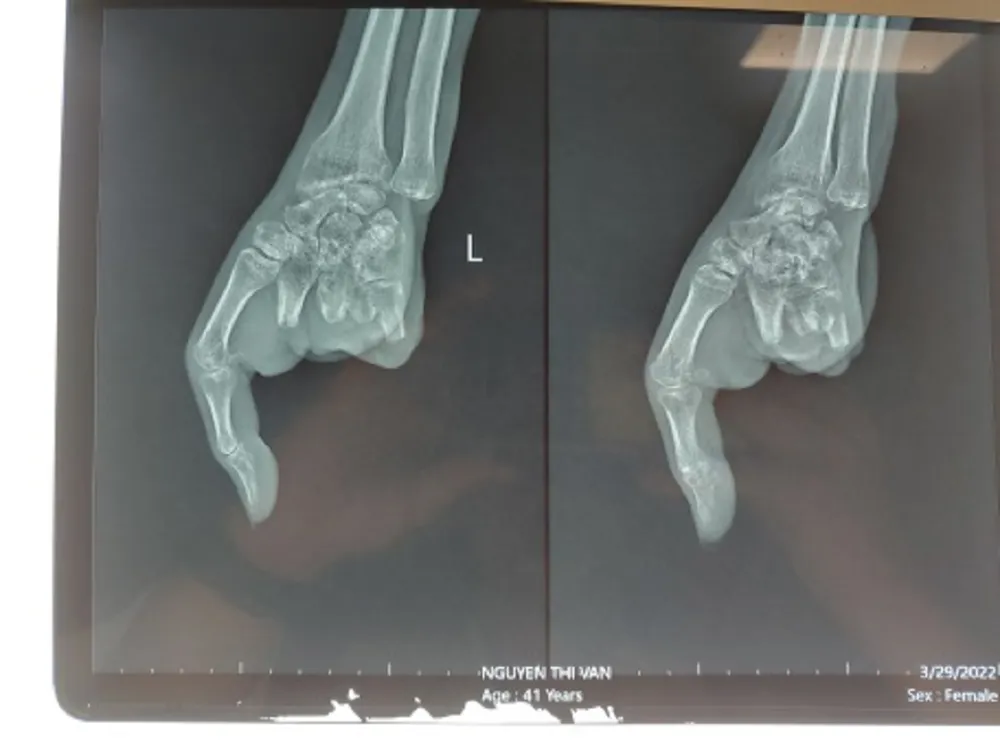

| Hình chụp X-quang bàn tay trái trước khi nối ngón. Ảnh: BVCC |

Cách đây khoảng ba tháng, bệnh nhân NTV (sinh năm 1981) bị máy xay thịt cuốn nát bàn tay trái, dập nát cả bốn ngón tay, tổn thương phức tạp. Các ngón tay thứ 2, 3, 4, 5 dập nát, không thể phục hồi, chỉ duy nhất còn ngón tay cái. Bác sĩ (BS) đã phẫu thuật tạo mỏm cụt từ ngón 2 đến ngón 5 bàn tay trái.